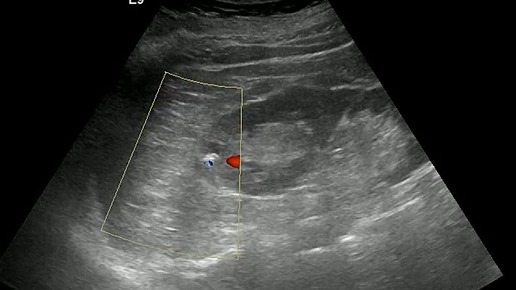

Ультразвуковые находки от врача УЗД Зорина Я.П.

Видео к статье: "Эти мерцающие камни" https://dzen.ru/a/aBmbayGKnRqpeaK7